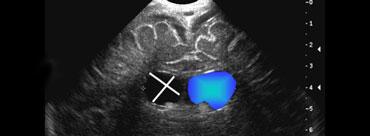

Nang đám rối mạch mạc

Trên siêu âm sau sinh, các nang của đám rối mạch mạc thường là phát hiện tình cờ và không có hậu quả lâm sàng.

Tuy nhiên, nang đám rối mạch mạc (Choroid Plexus Cyst – CPC) lại có ý nghĩa quan trọng đối với các bác sĩ sản khoa.

Trên siêu âm trước sinh, các nang này có thể là dấu hiệu gợi ý trisomy 18.

Khoảng một nửa số trẻ mắc Trisomy 18 có CPC trên siêu âm, nhưng hầu hết các trẻ này cũng sẽ có các bất thường khác trên siêu âm, đặc biệt ở tim, bàn tay và bàn chân.

Cần lưu ý đặc biệt đối với các nang xuất hiện gần lỗ Monro.

Mặc dù các nang này thường tự biến mất, vẫn cần theo dõi bằng siêu âm để xác nhận sự thoái triển.

Một số trường hợp có thể gây ra các triệu chứng tăng áp lực nội sọ do cản trở lưu thông dịch não tủy (DNT).